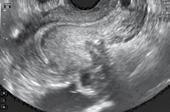

Pe baza ultrasonografiei transvaginale bidimensionale (EEV), trăsăturile considerate a fi asociate cu adenomioza sunt, după cum urmează: a) Uter mărit de volum cu asimetrie de grosime a pereților uterine (de exemplu, peretele anterior mai gros decât peretele posterior sau invers), fără legătură cu o posibilă prezență a unui nodul fibromatos; b) Chisturi intramiometriale; c) Insule hiperecogene intramiometriale; d) Umbre liniare fine (“în eventai”) determinate de modificările de structură intramiometrială; e) Striații liniare care pleacă de la nivelul zonei joncționale; f) Vas-cularizație intralezională evidențiată prin examen Doppler; g) Zonă joncțională neregulată; h) Zonă joncțională întreruptă. (1)

Identificarea a cel puțin trei semne ecografice din cele opt descrise este sugestivă pentru diagnosticul de adenomioză. Sensibilitatea, specificitatea și acuratețea diagnosticului ecografic endovaginal pe baza semnelor descrise variază între 80–86%, 50–96% și respectiv 68–86%. For-ma difuză de adenomioză este dificil de diferențiat de fibromatoza uterină mai ales în cazul ex-istenței unor fibroame de dimensiuni reduse.

Prin asocierea „question-mark sign“ cu cele opt criterii ecografice desemnate pentru di-agnosticul adenomiozei, sensibilitatea, specificitatea, valoarea predictivă pozitivă și valoarea pre-dictive negative ajung la 92%, 88%, 88% și respective la 92%. (2)

Di Donato Question mark

Orice semn ecografic din cele amintite scade rata de sarcini prin fertilizare in-vitro. Cu cât găsim mai multe semne ecografice cu atât rata de sarcină obținută in-vitro este mai scăzută. În unele studii statistice se afirmă că dacă există doar 3 semne dintre cele enumerate, posibilitatea existenței adenomiozei este foarte mare. Există încă multe capcane privind clasifi-carea adenomiozei și există anumite etape pe care trebuie să le urmărim pentru susținerea di-agnosticului de adenomioză. (3)

Trebuie precizată localizarea, dacă este o adenomioză focală sau difuză sau dacă este un adenomiom, dacă există leziuni chistice sau nu, care strat al miometrului este afectat, gradul de extensie care trebuie să fie cuantificat. Folosind ecografie 2D trebuie să facem distincția între adeomioză difuză sau focală sau adenomioame și în funcție de leziunile pe care le găsim și le descriem se poate stabili un scor și în acest fel putem aprecia mult mai exact rezultatele FIV pe care le obținem. Ecografia 3D oferă multiple avantaje care să precizeze forma de adenomioză și mai ales se poate face o analiză a modificărilor zonei joncționale. Zona joncțională apare ca un halou hipoecoic în jurul endometrului. A fost dovedit că o zonă joncțională ≥ 8 mm), sau neomogenă (diferența dintre grosimea maximă și cea minima mai mare de 4 mm) sugerează diagnosticul de adenomioză. Examinarea Doppler a leziunilor miometriale este necesar să fie utilizată. (4,5)